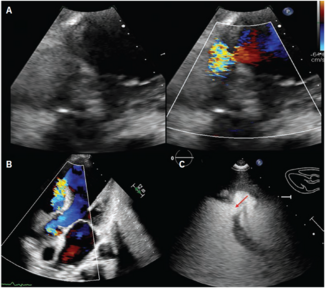

Hanif and Sheikh report a dramatic heart failure presentation caused by an acutely ruptured sinus of Valsalva aneurysm with right-atrial shunting. It was successfully treated in the cath lab with transcatheter closure using an Amplatzer Duct...